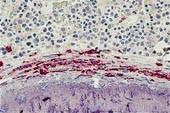

Ved beinaffeksjon utvikler 60 – 70 % radiologisk påvisbare lesjoner. Skjelettforandringene kan være forårsaket av mediatorsubstanser (13). Beinmargen er det hyppigst affiserte organ, bortsett fra hud. Det sees to forskjellige former av mastcelleinfiltrasjon: fokale mastcelleaggregater eller mer diffust utbredte mastcelleinfiltrater, ofte med økt granulopoese og eventuelt andre hematologiske forandringer. De fokale mastcelleaggregatene finnes ofte paratrabekulært med fibrose og eosinofile celler (fig 1a). Mastcellene er som regel atypiske, spolformede og fibroblastliknende, med få og små granulae (14, 15). Fibrosen kan være årsak til tørt aspirat. I perifert blod påvises ofte anemi, 30 % har leukocytose, 25 % trombocytopeni, 25 % eosinofili og 15 % har leukopeni og nøytropeni (15, 16). Eosinofili skyldes sannsynligens produksjon av interleukin 3 og 5 og granulocytt-makrofag-kolonistimulerende faktor i mastcellene (17). Perifer lymfeknutesvulst forekommer hos 25 % og sentral lymfeknutesvulst hos 20 % (15). I leveren sees mastcelleinfiltrater overveiende i portalfeltene (18) (fig 1c). Splenomegali finnes hos 50 – 70 % (17, 19). 35 – 80 % har abdominalsmerter. Hypersekresjon av syre pga. histaminfrigjøring kan gi dyspepsi og smerter i øvre abdominalhalvdel. Smerter i nedre abdominalhalvdel uten symptomlindring av H2-blokker kan kanskje skyldes ødem eller urticaria i gastrointestinaltractus. Diaré sees hyppig, mens malabsorpsjon er sjeldent. Ved malabsorpsjon er det mastcelleinfiltrasjon i lamina propria i tynntarmen (13, 19, 20).

Diagnosen mastocytose stilles først og fremst på grunnlag av histologiske funn i biopsier fra hud og beinmarg, sammen med sykehistorie og kliniske funn. Leverbiopsi og måling av histaminmetabolitter i urin kan være til hjelp. Beinmargsaspirat er som oftest normalt (pasient 2), og inneholder få og normale mastceller. Beinmargsbiopsi er derfor sentralt i diagnostikken av systemisk mastocytose, spesielt når det ikke er hudsymptomer eller objektive funn til stede. Når det gjelder biopsier, er fargemetoden viktig for å påvise mastceller. Farging for tryptase i sekretoriske granulae som er spesifikke for mastceller, er den viktigste (fig 1b). Ved farging med giemsa og toluidinblått kan man demonstrere de metakromatiske mastceller (fig 1c), men basofile leukocytter kan også utvise metakromasi. Da kan immunhistokjemi med monoklonale antistoffer være avklarende. c-kit (CD117) er spesifikk for mastceller, mens laktosylceramid (CDw17) og α -reseptor for interleukin 3 (CD123) er spesifikk for basofile leukocytter (5).

g portalfelter), milt og nyrer. I portalfeltene så man i tillegg infiltrater med atypiske mastceller (fig 1c). Pasienten hadde en systemisk mastocytose assosiert med myelodysplastiske forandringer (type 2), og døde under et bilde av en myeloproliferativ lidelse. Sykehistorien viser at systemisk mastocytose kan ha et raskt og dødelig forløp.